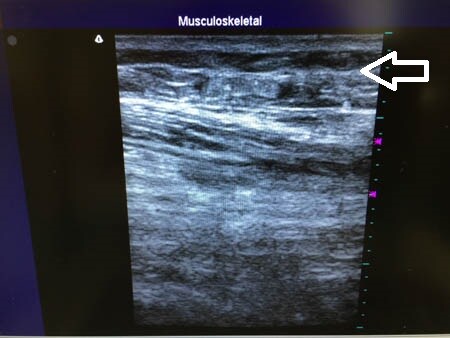

右太もも後面。